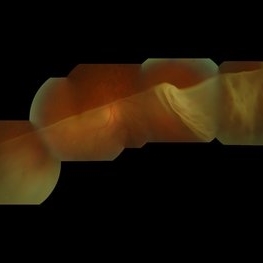

Buckle Eroding Through to Subretinal Space

A high myope who underwent conventional retinal detachment surgery 20 years ago was noted to have an eroding scleral explant in the sub-retinal space.

Photographer: Janet Wigmore, Auckland Eye. Auckland, New Zealand.

Condition/keywords: extruding